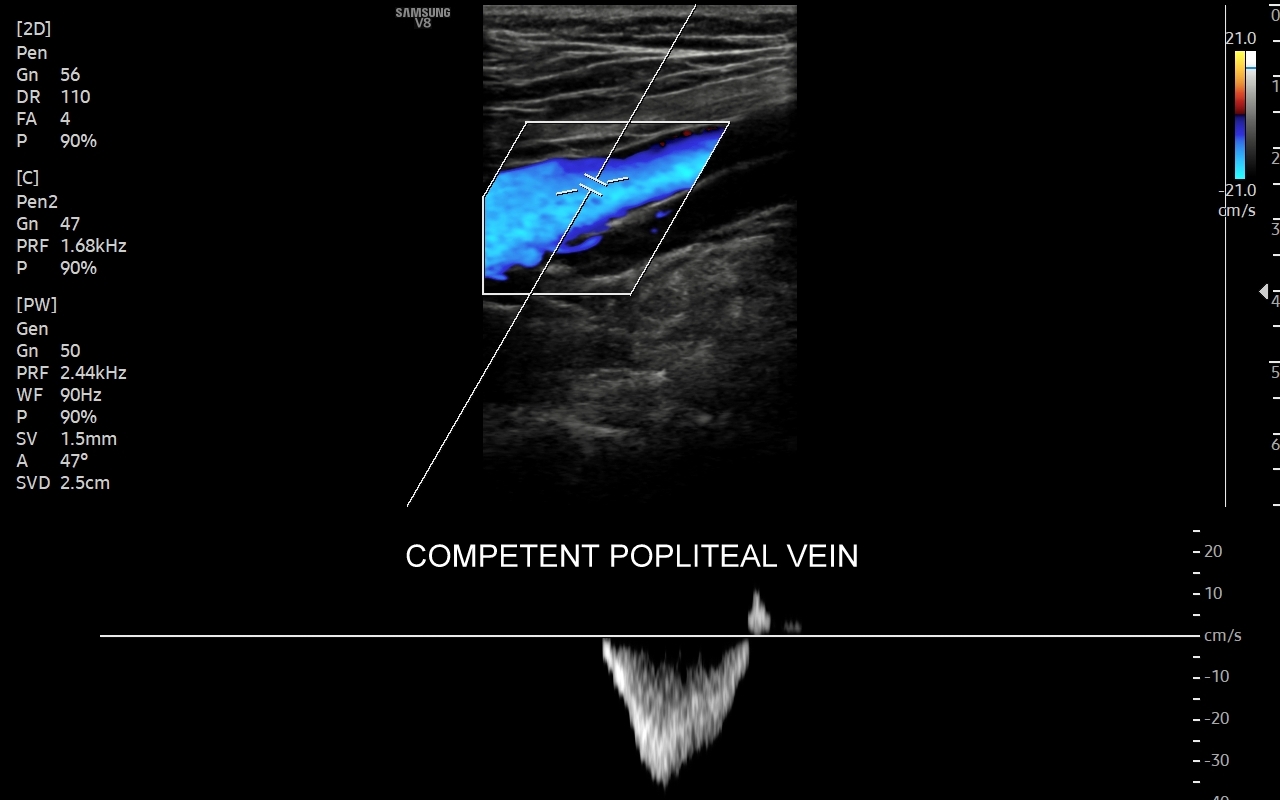

Żyły kończyn dolnych. W obrębie żył kończyn dolnych znajdują się dwa zasadnicze układy żylne – układ żył głębokich i układ żył powierzchownych. Oba układy łączą się razem bezpośrednio w okolicy pachwiny oraz dołu podkolanowego; poza tym na różnych poziomach kończyny przy pomocy żył przeszywających. Każde połączenie układu głębokiego i powierzchownego posiada naturalnie zastawkę, która zapobiega cofaniu się krwi w niewłaściwym kierunku. Prawidłowym kierunkiem jest przepływ z układu powierzchownego do głębokiego oraz ku sercu. Zarówno w układzie powierzchownym, jak i głębokim lokalizować mogą się poważne choroby takie jak zakrzepica, czy niewydolność żylna.

Co napędza przepływ krwi w żyłach ku sercu? Główną siłą napędzającą przepływ krwi z nóg są skurcze mięśni łydek i ud. Aby krew pod wpływem grawitacji nie cofała się z powrotem w dół niezbędne są prawidłowo funkcjonujące zastawki w żyłach kończyn. Z kolei z górnych partii ciała siłą napędzającą powrót krwi do serca jest grawitacja oraz ujemne ciśnienie w klatce piersiowej zależne od pracy oddechowej. Prawidłowy i niezakłócony przepływ krwi w żyłach zapobiega powstawaniu zakrzepicy oraz powikłań niewydolności żylnej.

Badanie USG żył kończyn dolnych najczęściej wykonywane jest w ramach diagnostyki niewydolności żył powierzchownych oraz ich objawów w postaci pajączków żylnych, żylaków kończyn dolnych, obrzęków i owrzodzeń żylnych. Kolejnym pod względem częstości wskazaniem do badania Doppler żył jest podejrzenie zakrzepicy żył głębokich kończyn dolnych, monitorowanie leczenia zakrzepicy oraz ocena jej powikłań odległych. Powikłaniem nieleczonej zakrzepicy żył głębokich może być zespół pozakrzepowy manifestujący się masywnymi obrzękami kończyny i zaburzeniami troficznymi. Badanie USG Doppler żył kończyn dolnych często uzupełniane jest oceną układu żył centralnych w miednicy i jamie brzusznej. W tych obszarach również pojawiać się mogą żylne zmiany zakrzepowe, niedrożności żył, a nawet zmiany nowotworowe.

Podczas najczęściej przeprowadzanego badania, tj. USG Doppler kończyn dolnych, oceniane są żyły głębokie oraz powierzchowne na całej długości kończyny – od stóp aż do pachwiny. Czasami mogą zaistnieć wskazania do rozszerzenia badania na wyższy poziom układu żylnego, tj. na żyły biodrowe w miednicy i żyłę główną dolną w jamie brzusznej. Badanie USG żył jest badaniem dynamicznym, tzn. oprócz oceny wyglądu żył wykonuje się różnorodne próby czynnościowe, takie jak kompresja, głębokie oddychanie, próba Valsavy, podczas których rejestruje się przepływy krwi w żyłach.

W przypadku oceny wydolności żył oraz kwalifikacji Pacjenta do zabiegu na żyłach lub na żylakach kończyn dolnych dynamiczne badanie dopplerowskie żył wykonuje się także w pozycji pionowej. Przy opisanych próbach czynnościowych wykorzystuje się specjalne właściwości sprzętu USG, tj. tryby badań dopplerowskich, tryby duplex i triplex, a także angografię sonograficzną dostępną w aparatach wysokiej klasy.

Jak przebiega badanie USG Doppler żył? Badanie przeprowadzane jest w pozycji pionowej oraz w poziomej, tj. najpierw pacjent stoi na dedykowanym podeście, a następnie spoczywa na leżance. Pionowa pozycja ciała w powiązaniu ze zjawiskiem grawitacji sprzyja wypełnianiu się żył w kończynach dolnych, a przez to umożliwia stwierdzenie stanu niewydolności żyły, czyli wstecznego cofania się krwi do nogi. Wypełnione żyły ułatwiają również wykrycie potencjalnej zakrzepicy żylnej.